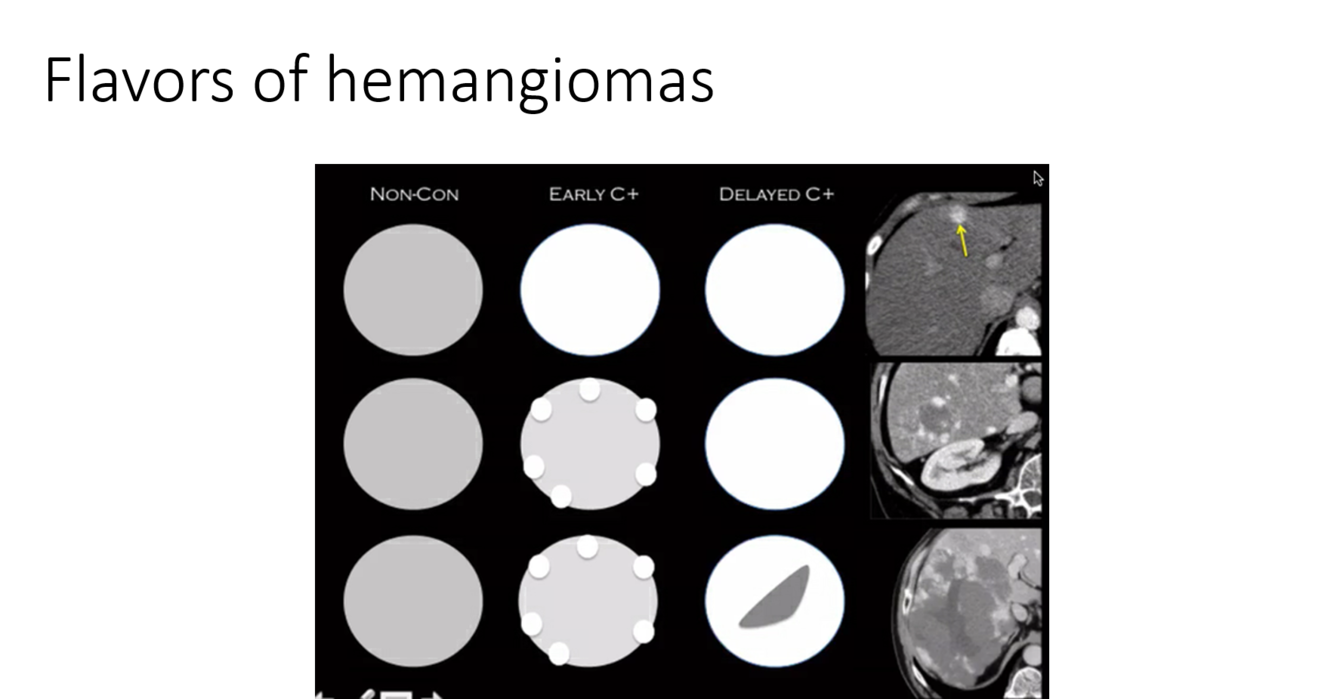

get delayed images (10-20 min). this is most likely a cavernous hemangioma

You think that the following is a hemangioma in a fatty liver, but the mid-level provider doesn’t believe you. The patient has abandoned pacer leads and can’t get an MRI. What is your next step?

Tagged RBC scan to look for hemangiomas

tagged RBC scan demonstrating hemangiomas in the liver